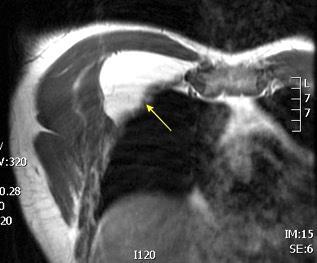

Tumor desmoide (“Fibromatosis agresiva”)

T1: Isointensos con músculos.

T2: Señal intermedia y de alta intensidad.

Presencia frecuente de áreas curvilíneas y lineales dentro de la lesión

Mansour J et al. Diagnostic and Imaging Approaches to Chest Wall Lesions. Radiographics 2022